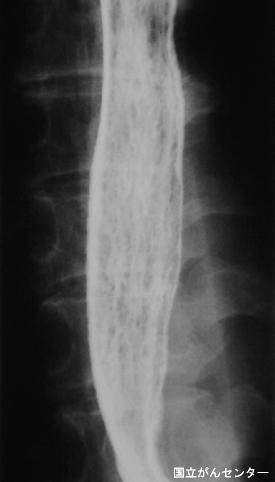

Candidiasis de Esófago originario de cáncer avanzado del estómago

Enfermedad Inflamatoria - Ulcerativa/Esofagitis moniliásica

parte(separada por órganos)

esófago/mas de dos

método de exámen

Rayos X

diámetro mayor del tumor

1 - 9